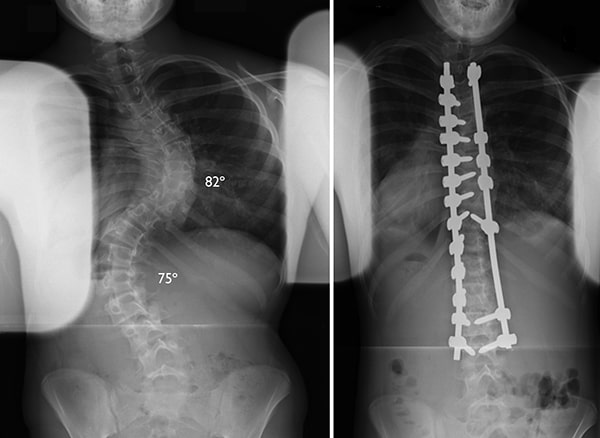

- 2. Scoliosis A sideways curvature of the spine that often develops during growth spurts.